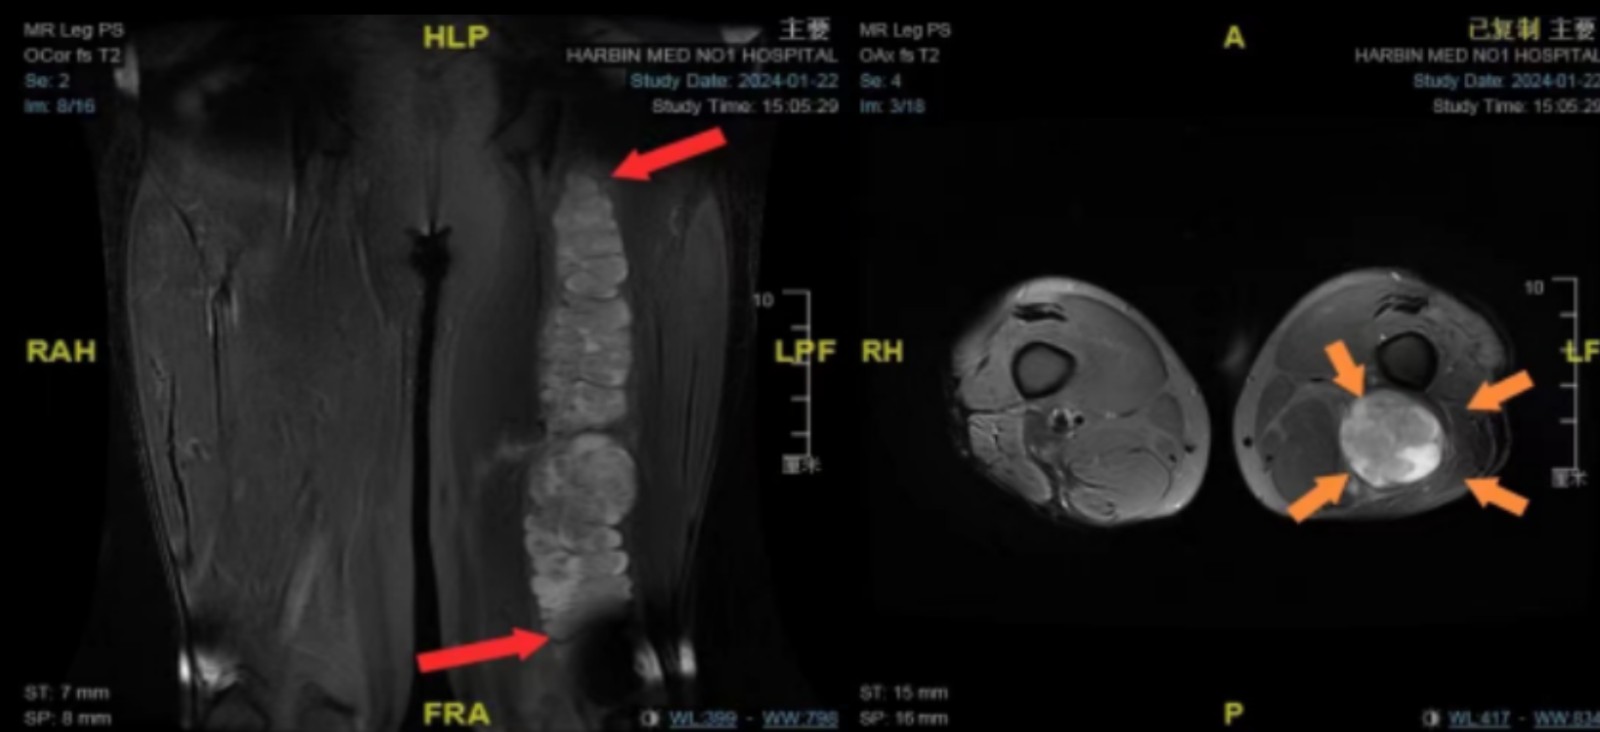

患者入院后完善相关检查(下肢超声、下肢MRI、下肢血管造影、肌电图),检查结果提示巨大肿物与一侧坐骨神经关系密切,并且大的动脉血管被病变包绕,手术切口要1250px长,由于患者患有糖尿病,术后切口的愈合使得难度加大。

通过术中超声,拟定病变边界及切口范围:病变顶端位于左侧臀部,臀大肌深方,最低端达到膝盖下方外侧,总长近40厘米;术中通过神经外科显微镜,观察到病变附着在负责支配下肢运动的坐骨神经上,手术过程中稍有不慎就可能导致坐骨神经损伤,加重下肢活动障碍的情况。在电生理监测的保驾护航下,最大程度保护神经功能,仔细将神经分离,手术历经7个多小时,完整切除下肢巨大神经源性肿瘤。